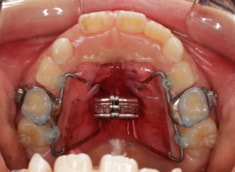

治療法:拡大装置+フルパッシブブラケット(クリアスナップ)+フェイスマスク+舌トレーニング+前歯部エラスティック

治療開始時